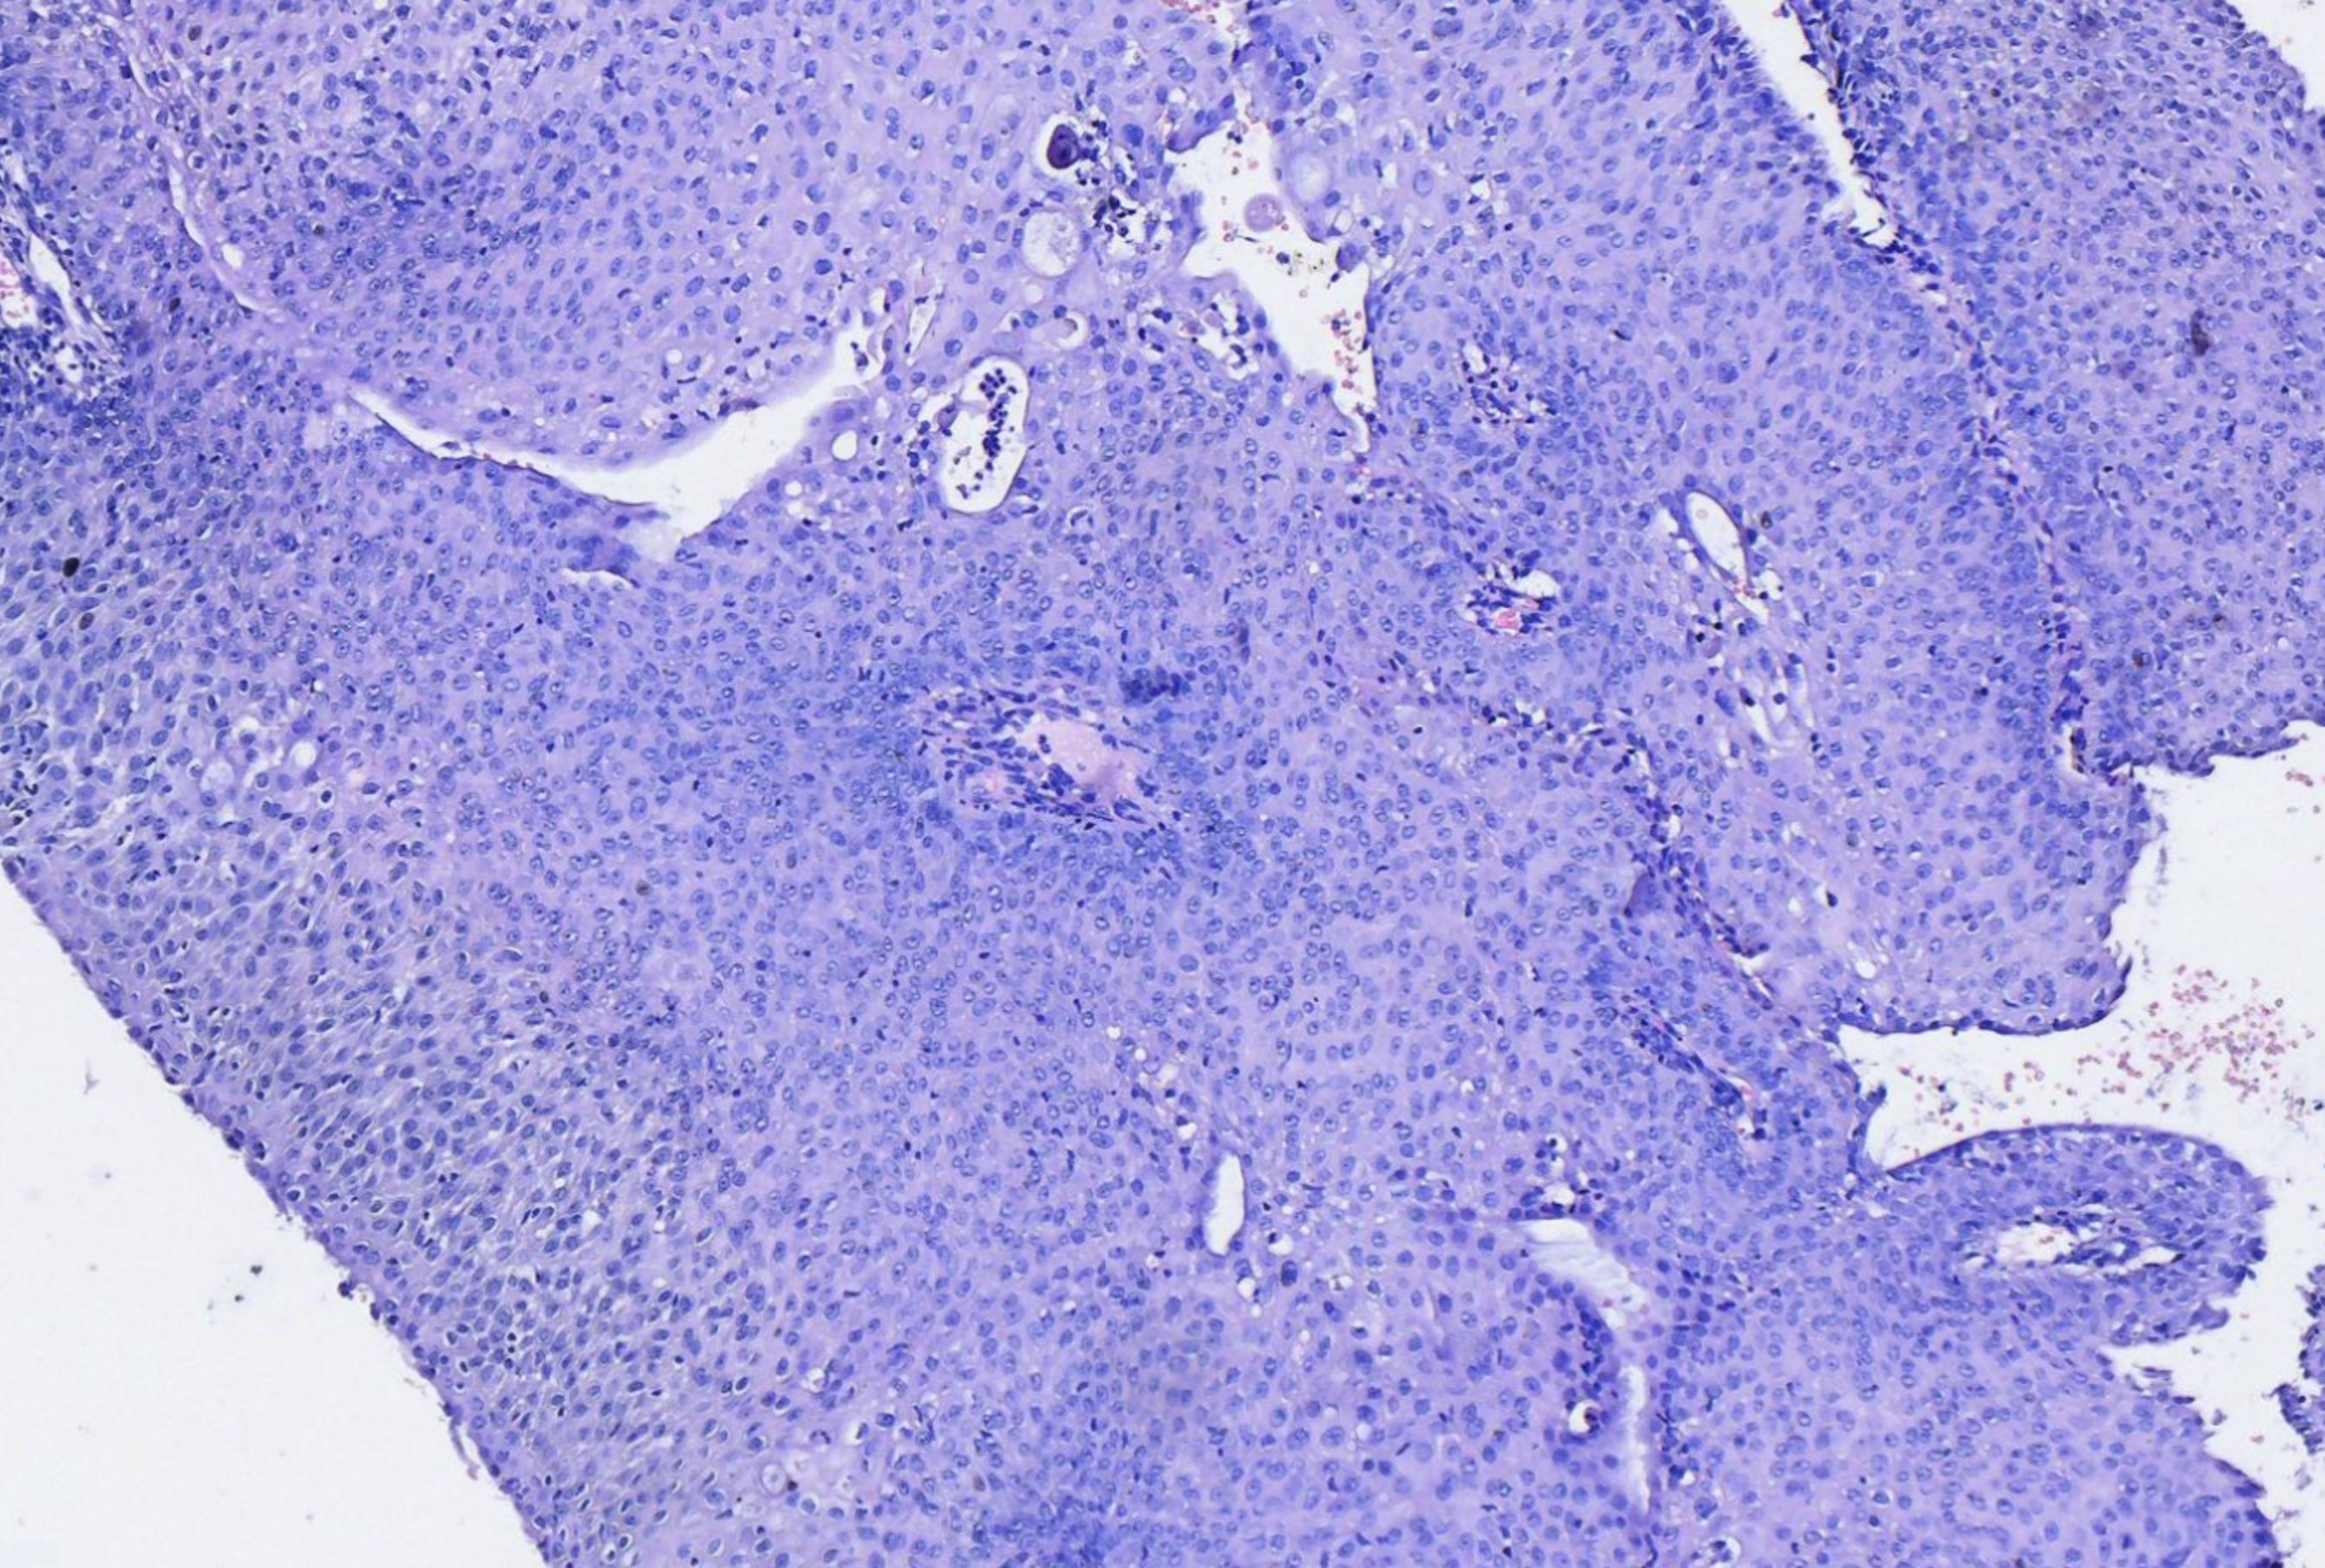

湿疣还是疣状癌?

性别年龄35岁临床诊断

一般病史发现宫颈赘生物一周

标本名称宫颈活检

大体所见碎组织数枚灰白

考虑:湿疣样变!

做一下P16和Ki67看看有没有高级别。

这个要除外疣状癌。

注意包埋方向,除外湿疣性鳞癌

老师,不忙了反馈一下最终结果。  我感觉这个还是疣状癌。

• assist:  上级医院会诊结果,乳头状瘤样病变伴cin1